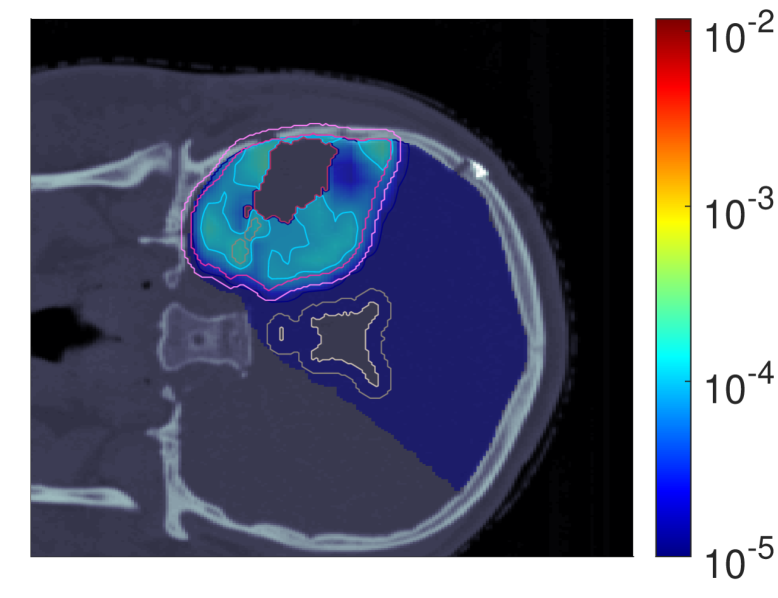

Figure 2 shows the optimal slice images of the dose (left), dose-averaged LET (middle) and POLO distribution (right). On the underlying CT scan, the tumor volumes are marked by violet to purple contours, while the VS (ventricles and 4 mm4\text{\,}\mathrm{mm} fringe) is outlined in white and gray. We observe the high-dose region covering all of the GTV, with a largely homogeneous transition to the clinical and planning target volumes (CTV, PTV), and a moderate to severe overlap to the VS. The dose-averaged LET distributes in layers, with increased values around the contour edge of CTV/PTV and local peaks at the distal ends of the proton beams. Accordingly, hot spots on the POLO map are found in regions where dose and dose-averaged LET scale up, or close to the VS. Beyond the PTV, the POLO map reveals cold spots, due to the steepness of the dose and dose-averaged LET gradients.

dRBE,fxd_{RBE,fx}ABCD ldl_{d}ABCD ppABCD

Refer to caption Refer to caption Refer to caption

NTCP:45.59 %NTCP:$45.59\text{\,}\mathrm{\char 37\relax}$ABCD

Figure 2: Optimal 2D slice images of the RBE-weighted fractional dose dRBE,fxd_{RBE,fx}, the dose-averaged linear energy transfer ldl_{d} and the probability function values pip_{i} for the baseline plan. The dose distribution (left) shows high target coverage with decreasing exposure beyond the CTV/PTV margins, but also visibly overlaps with parts of the VS. Meanwhile, for the dose-averaged LET (middle), layered homogeneity in the target volumes and local maxima at the distal ends of the proton beams can be observed. This results in more pronounced levels of POLO values within the target volumes, particularly in the presence of local dose-averaged LET maxima and in the environment of the VS. Referring back to the POLO model from Equation 1 and (3), we can expect exactly this type of coherence between the model output, the physical input feature profiles and the increased local risk near the VS. The baseline treatment plan exhibits a complication risk of 45.59 %45.59\text{\,}\mathrm{\char 37\relax} after evaluation of the POLO distribution with NTCPpNTCP_{p}.